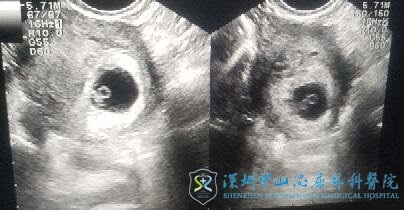

第二个月H女士就移植了这2个优质卵裂胚胎。开奖日血HCG:1293mIU/ml,怀上了!!!喜悦的心情让H女士热泪盈眶,没想到卵巢储备差也能一次就中。很快夫妻俩迎来了一超,B超提示宫内双孕囊双胎妊娠,由于黄女士身高仅150cm,体重才80斤,双胎母婴风险太高,为了优生优育,降低母亲和孩子的风险,徐士儒医生建议减为单胎妊娠,虽然夫妻俩很是舍不得,但是为了保证孩子的健康,最终他们选择减胎。2016年的3月H女士顺利剖宫产分娩女儿“小豆苗”,孩子非常健康,活泼可爱。

2019年3月,在女儿3岁之际,H女士再次到深圳中山妇产医院找到了徐士儒医生,3年过去了,B超检查H女士双侧卵巢只有1个小卵泡,H女士忐忑的问道还有希望吗?徐士儒医生温柔而坚定告诉夫妻俩,你那么年轻,只要有卵就有用。